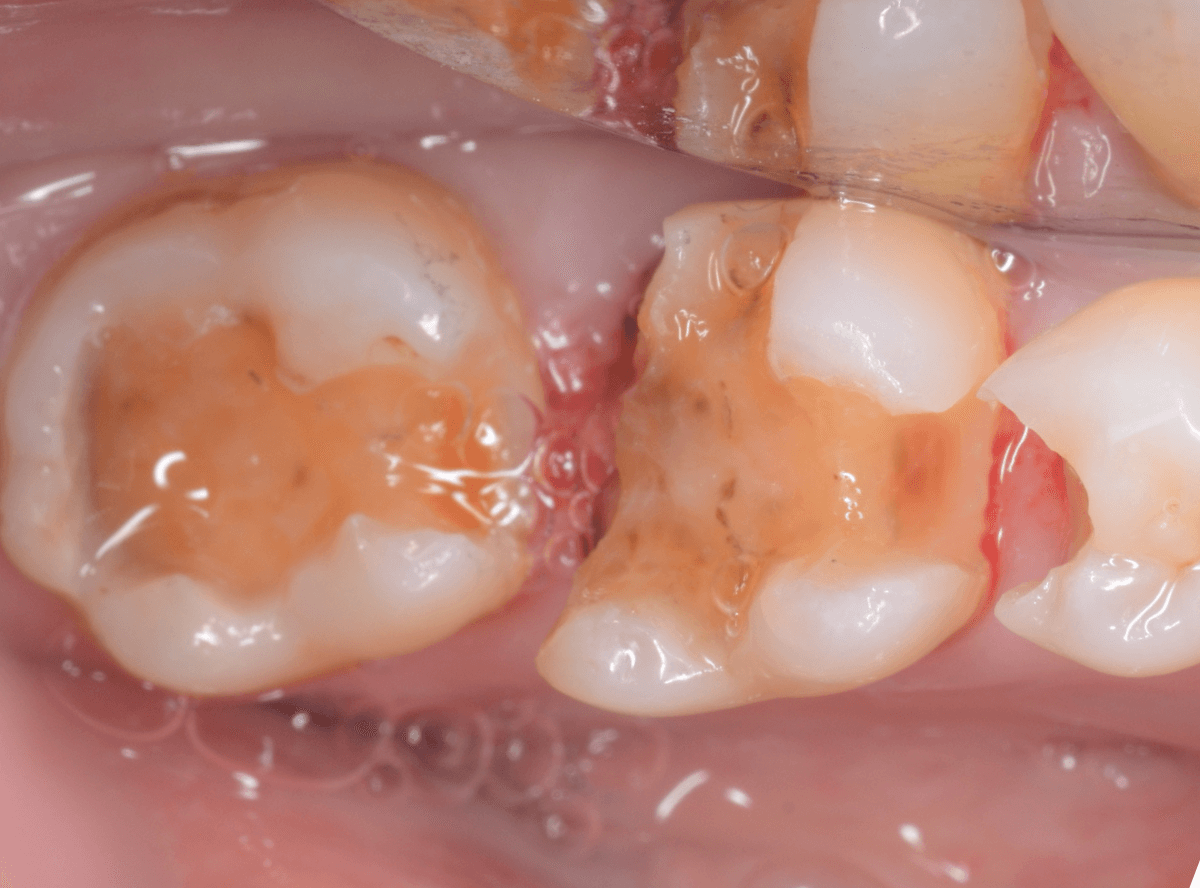

奥の歯の虫歯を全て除去したところです。

やはりかなり深くて広い虫歯でした。

続けて手前の小臼歯の虫歯の治療に入ります。

余談ですが、この方は小臼歯が前後反対に生えている珍しい方です。

少し削ると、こちらもすぐに虫歯が出てきました。

こちらの歯もかなり虫歯が深いです。

神経に達してしまいそうな虫歯です。

慎重に虫歯を除去します。

隣りの歯の側面にも虫歯が進行しているのがわかります。

3本、全ての虫歯を除去しました。